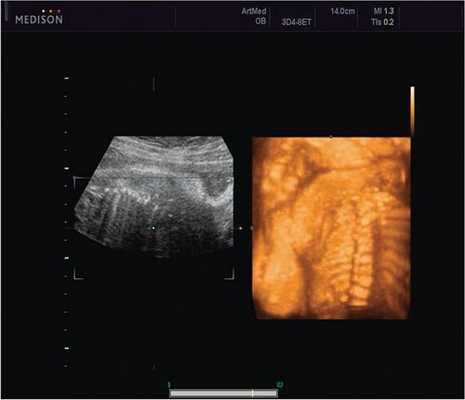

Революцией в пренатальной ультразвуковой диагностике явилось появление объемной эхографии, которая, обладая такими качествами, как неинвазивность, безопасность и возможность многократного применения у одной пациентки, имеет высокую информативность в исследовании анатомии плода и изучении его фенотипа. При применении различных режимов объемной эхографии абсолютно очевидно их преимущество по сравнению с обычным сканированием. Детально можно изучить лицо плода (рис. 1-4) в различные сроки беременности, начиная со сроков первого пренатального скрининга в 11-14 нед, конечности плода, причем не только их наличие и положение (рис. 5, 6), но и состояние и количество пальцев (рис. 7-9) как на руках, так и на ногах. Также можно изучить позвонки плода (рис. 10), состояние твердого нёба (рис. 11, 12), строение наружного уха (ушной раковины) (рис. 13), состояние основных швов черепа и родничков, исключая их преждевременное закрытие при кранисиностозах (рис. 14, 15).

Пациентка К., 26 лет, обратилась в клинику в 23 нед беременности. Беременность первая. Исследование проводилось на аппарате Accuvix-XQ (Samsung Medison) с использованием режима поверхностной объемной реконструкции 3D/4D. Показатели фетометрии полностью соответствовали сроку беременности. В процессе сканирования позвоночника во фронтальной и сагиттальной плоскостях выявлена угловая деформация позвоночника в грудном отделе, протяженностью около трех позвонков. В поперечной плоскости сканирования нарушения структур и целостности тканей не было обнаружено. В режиме 3D/4D реконструкции было выявлено асимметричное расхождение ребер правой и левой стороны грудной клетки (рис. 4).

Ребра левой стороны были сближены, межреберные промежутки уменьшены по сравнению с противоположной стороной (рис. 5, 6). Другой патологии у плода не было выявлено. Заподозрен врожденный сколиоз, основой которого является наличие боковых полупозвонков (hemivertebrae) или боковых клиновидных позвонков. В 26 нед ультразвуковая картина сохранялась. При проведении трехмерной эхографии получено отчетливое изображение асимметрии реберных дуг и сколиотическая деформация позвоночника.